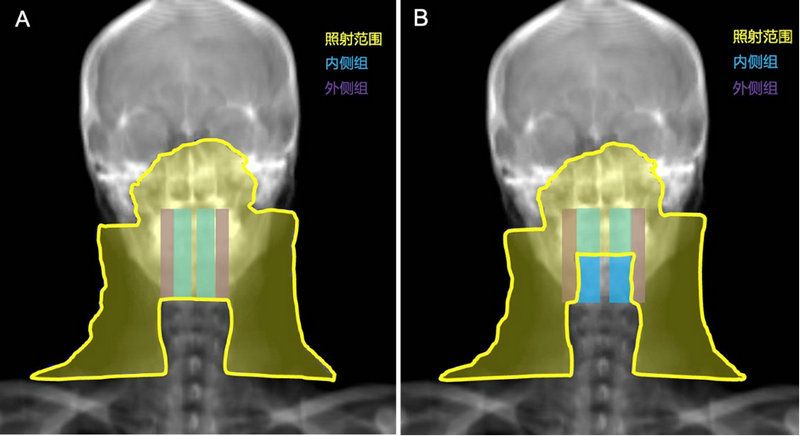

鼻咽癌预防照射范围示意图

A对照组:内、外侧组咽后淋巴结区均接受预防照射(左)

B试验组:内侧组咽后淋巴结区豁免预防照射(右)